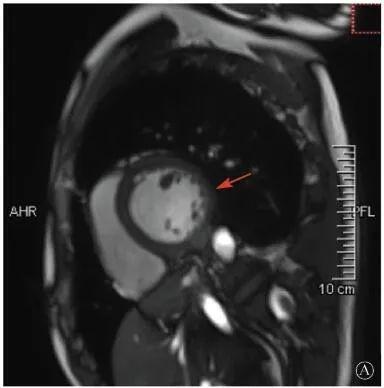

案例介紹:患者男性,20歲,因為"胸痛4個月,加重1月余"于2019年7月10日入院?;颊?019年4月無明顯誘因出現(xiàn)心前區(qū)隱痛,VAS 3分,無放射,無胸悶、憋氣、活動后氣短,每月發(fā)作1~2次,未在意。同年5月體檢發(fā)現(xiàn),肌酸激酶(CK)2928 U/L、肌酸激酶MB質量(CK-MB)46 U/L、心肌肌鈣蛋白I(cTnI)0.055 ng/ml。6月初,患者"感冒"后出現(xiàn)心前區(qū)疼痛加重,為過電樣疼痛,VAS 5分,無放射,持續(xù)約30~60 min可好轉,胸痛每周約發(fā)作2次,否認呼吸困難、胸悶、心悸,否認活動耐量下降。6月8日,患者就診于外院查血生化:CK 1 215→1433 U/L,CK-MB 47 U/L,cTnI 30.17→31.79 ng/L;血脂(-);抗核抗體譜(-);超聲心動圖:左室增大,左室舒張末內(nèi)徑57 mm,左室射血分數(shù)39%,輕度二尖瓣關閉不全;磁共振心肌灌注延遲動態(tài)成像(圖1):左室稍增大,收縮功能稍減低;基底部至心尖部左室下壁及側壁、心尖部左室前壁心外膜下心肌纖維化,考慮非缺血性心肌??;肌電圖:肌源性損害(偏慢性)。診斷"多發(fā)性肌炎、心肌損傷",予患者倍他樂克緩釋片23.75 mg/d、培哚普利0.5 mg/d、螺內(nèi)酯20 mg/d口服,患者未再出現(xiàn)心前區(qū)疼痛,但步行1 km左右會出現(xiàn)氣短、乏力。為進一步明確心力衰竭病因收入我院?;颊呱细咧衅鸪霈F(xiàn)體育課等劇烈活動后雙下肢明顯乏力,不能耐受1 km長跑類運動,日常體力活動不受影響,否認肌肉酸痛等不適。此次發(fā)病以來,一般情況尚可,否認尿量減少,體重無明顯變化。既往史:否認高血壓、冠心病、糖尿病病史。個人史:否認特殊毒物藥物接觸史,無煙酒嗜好?;橛贰⒓易迨罚何椿槲从?,否認家族類似病史,否認遺傳病史。入院查體:脈搏69次/min,血壓112/70 mmHg,指氧(自然狀態(tài))98%,體質指數(shù)21.1 kg/m2;無皮疹;雙肺呼吸音清;心律齊,未聞及雜音;肝脾不大;雙側腓腸肌肥大,肌肉無壓痛;四肢肌力Ⅴ級、肌張力正常。雙下肢不腫。輔助檢查:入室床旁超聲心動圖提示左室壁運動普遍減低,心尖部、左室下后壁為著,肌小梁增多。

左室壁較廣泛心外膜下延遲強化,可見左室下后壁肌小梁增多(箭頭所示)

圖1 患者外院磁共振心肌灌注延遲動態(tài)成像